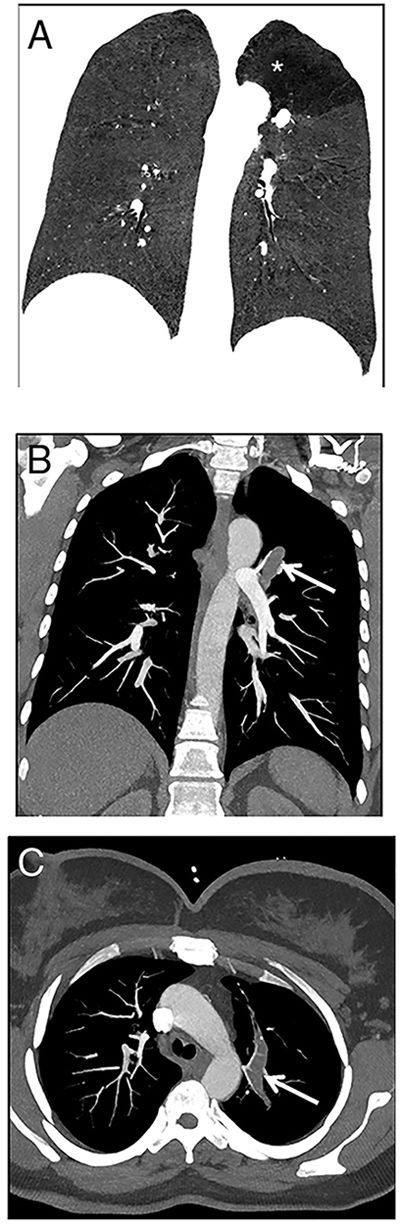

A 22-year-old woman was referred to our emergency radiology unit with sudden onset of shortness of breath and left-sided chest pain. The chest radiography revealed left hilar tubular opacite (arrow) and hyperaeration (asterisk) in the upper zone of the left lung (Fig. 1). The contrast enhanced computed tomography (CT) showed a non-contrast enhancing tubular mass that was seen extending from the left hilum, with surrounding hypoattenuation of the apicoposterior segment of the left upper lobe (asterisk), a finding indicative of hyperinflation (Fig. 2A). There was also no connection between the non-contrast tubular mass (arrows) and pulmonary artery of the apicoposterior segment in the left upper lobe (Fig. 2B–C). CT findings were also including mucocele and occlusion of the bronchus central to the mucocele. CT results (mucocele with hyperaeration of the adjacent lung parenchyma) were considered pathognomonic for bronchial atresia. Surgical treatment was no performed because the patient refused operation.

The reformat coronal CT at maximum inspiration (A) shows a non-contrast enhancing tubular lesion with surrounding hypoattenuation of the apicoposterior segment of the left upper lobe (asterisk), a finding indicative of hyperinflation. The coronal CT scan also demonstrates aerial trapping in the apicoposterior segment of the left upper lobe. The contrast enhanced maximum intensity projection images (B and C) reveal no connection between the non-contrast tubular lesion (arrows) and pulmonary artery of the apicoposterior segment in the left upper lobe.

The bronchial atresia is a congenital abnormality resulting from focal interruption of a lobar, segmental, or sub segmental bronchus with associated peripheral mucus impaction and associated hyperinflation of the obstructed lung segment. In bronchial atresia, cause of hyperinflation of the adjacent lung is collateral air drift. Unlike congenital lobar overinflation, there is no ball-valve effect in this condition. Hence, the lobar or segmental hyperinflation is mild.1

Radiologically, bronchial atresia is associated with a triad of findings: focal interruption of a bronchus; associated distal mucus impaction (bronchocele) that is visible as a branching tubular or ovoid area of increased attenuation; and associated hyperinflation of the obstructed pulmonary segment.2 Bronchial atresia should be kept in mind in patients with shortness of breath and chest pain.